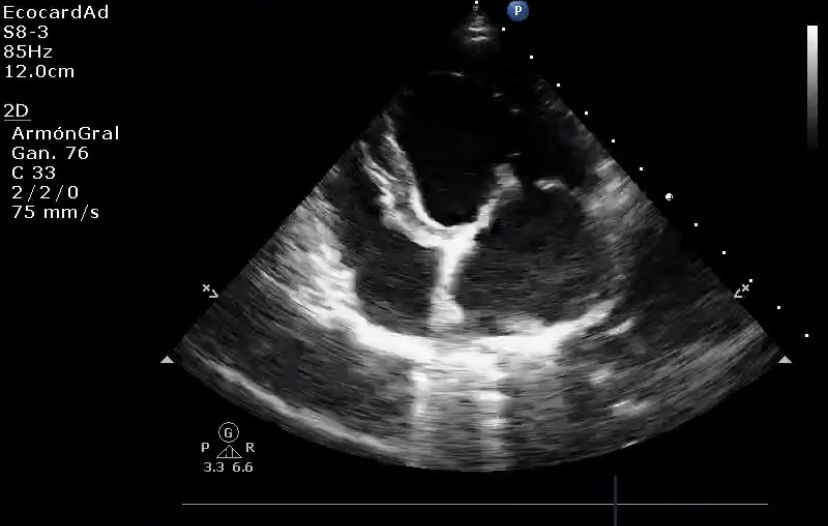

MMVD is a common cardiac disease in dogs and can be present in any breed, though is particularly seen in some small breeds such as the Cavalier King Charles Spaniel and Dachshund.